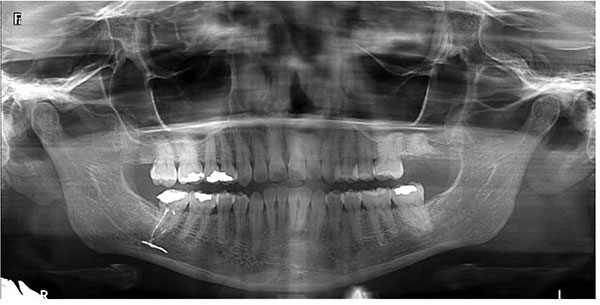

ქვედა ყბაზე კბილები ისეა განლაგებული, რომ ფესვის მწვერვალების ქვეშ მცირე მანძილის დაშორებით ქვედა ყბის არხი გადის, რომელშიც ქვედა ყბის ნერვი მდებარეობს. ამიტომ ქვედა ყბის კბილების არხების მკურნალობისას შესაძლოა გადატანილი საბჟენი მასალა სწორედ ამ არხში მოხვდეს და ნერვზე კომპრესია მოახდინოს, რაც იწვევს ნერვის გამტარებლობის დარღვევას და მგრძნობელობის მოშლას, დროთა განმავლობაში კი ნერვის ატროფიას. ასეთ შემთხვევაში ექიმის მხრიდან დაუყოვნებელი მოქმედებაა საჭირო, კერძოდ კი მიკროქირურგიის გზით ნერვის გათავისუფლება უცხო მასისგან სანამ ნერვის დაზიანება შეუქცევადი გახდება. 3დ რენტგენოლოგიური გამოკვლევით დგინდება მასის ზუსტი ლოკალიზაცია და პაციენტი გადამისამართდება ყბა-სახის ქირურგთან. მიკროქირურგიის ჩატარება 48 საათის შემდეგ ამცირებს წარმატების შანსს, რის გამოც პაციენტს მუდმივად ექნება წვის და დაბუჟების შეგრძნება ღრძილების, ტუჩისა და ნიკაპის არეში.